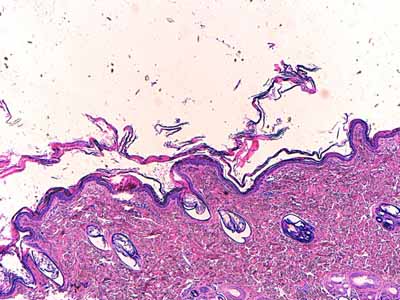

À l’examen histologique, on observe un épiderme d’épaisseur normale à discrètement hyperplasique avec un très fin bourgeonnement à peine ébauché des couches basales donnant à l’épiderme un aspect plicaturé ou festonné (Photo 2). Il apparaît souvent hyperpigmenté. Les couches les plus basales de l’épiderme apparaissent surpeuplées avec une surabondance d’images nucléaires (aspect en faveur d’une rétention cellulaire)(Photo 4).

L’épiderme présente une hyperkératose orthokératosique compactée qui reste alvéolaire et laminée (Photo 2).

Les annexes épidermiques sont normalement représentées, le cycle folliculaire est normal. Le derme n’apparaît pas particulièrement inflammatoire (Photo 1). Aucun élément figuré n’est visible, ni parasitaire, ni fongique.

Photo 2 (Hémalun Eosine X 40) : L’épiderme est le siège d’une hyperkératose orthokératosique

laminée parfois compactée, intéressant également les ostia folliculaires. Le derme semble silencieux.